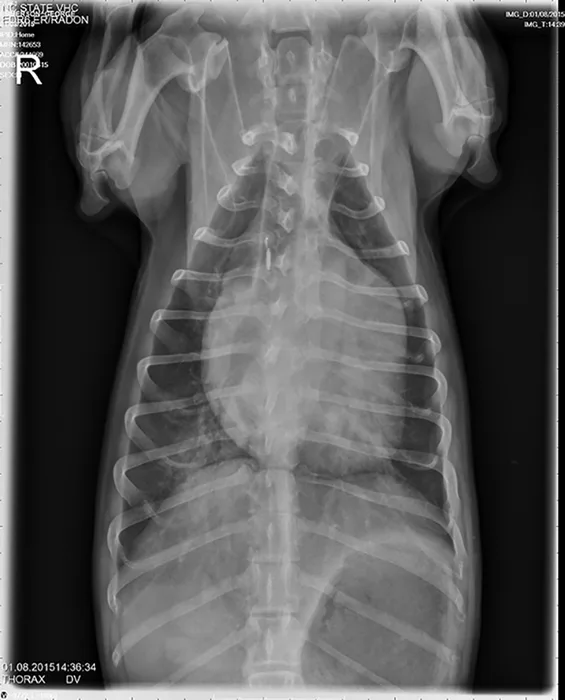

A grade IV/VI systolic heart murmur was detected with a point of maximal intensity over the left apical region; heart rhythm was regular, and pulses were strong and synchronous. Lung sounds were increased, with no crackles or wheezes. Thoracic radiographs showing progressive left atrial and ventricular enlargements, mildly enlarged pulmonary veins, a moderate patchy unstructured interstitial pattern in the right caudal lung lobe, and a mild unstructured interstitial pattern in the left caudal lung lobe were consistent with pulmonary edema. Caudal mainstem bronchi were compressed on lateral projections secondary to the cardiomegaly and left atrial enlargement. Radiographic findings were compatible with left-sided congestive heart failure (CHF) secondary to MV disease.

Lateral and DV views showing mild CHF in a dachshund with mitral valve disease.